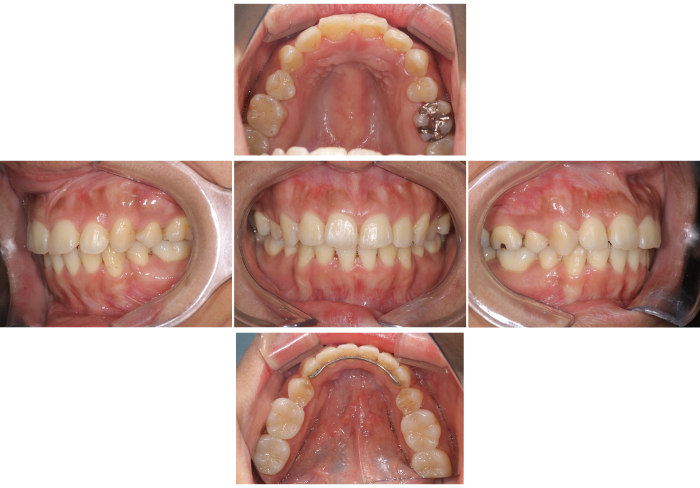

矯正+補綴ジルコニアクラウン

Before

After

患者の症状 歯が重なっており見た目が悪い 銀歯が気になる

治療方法  歯並びはワイヤーを用いて改善後に銀歯はジルコニアクラウンに変更

治療結果  歯並びの改善とともに審美はもちろん機能的にも改善することができた